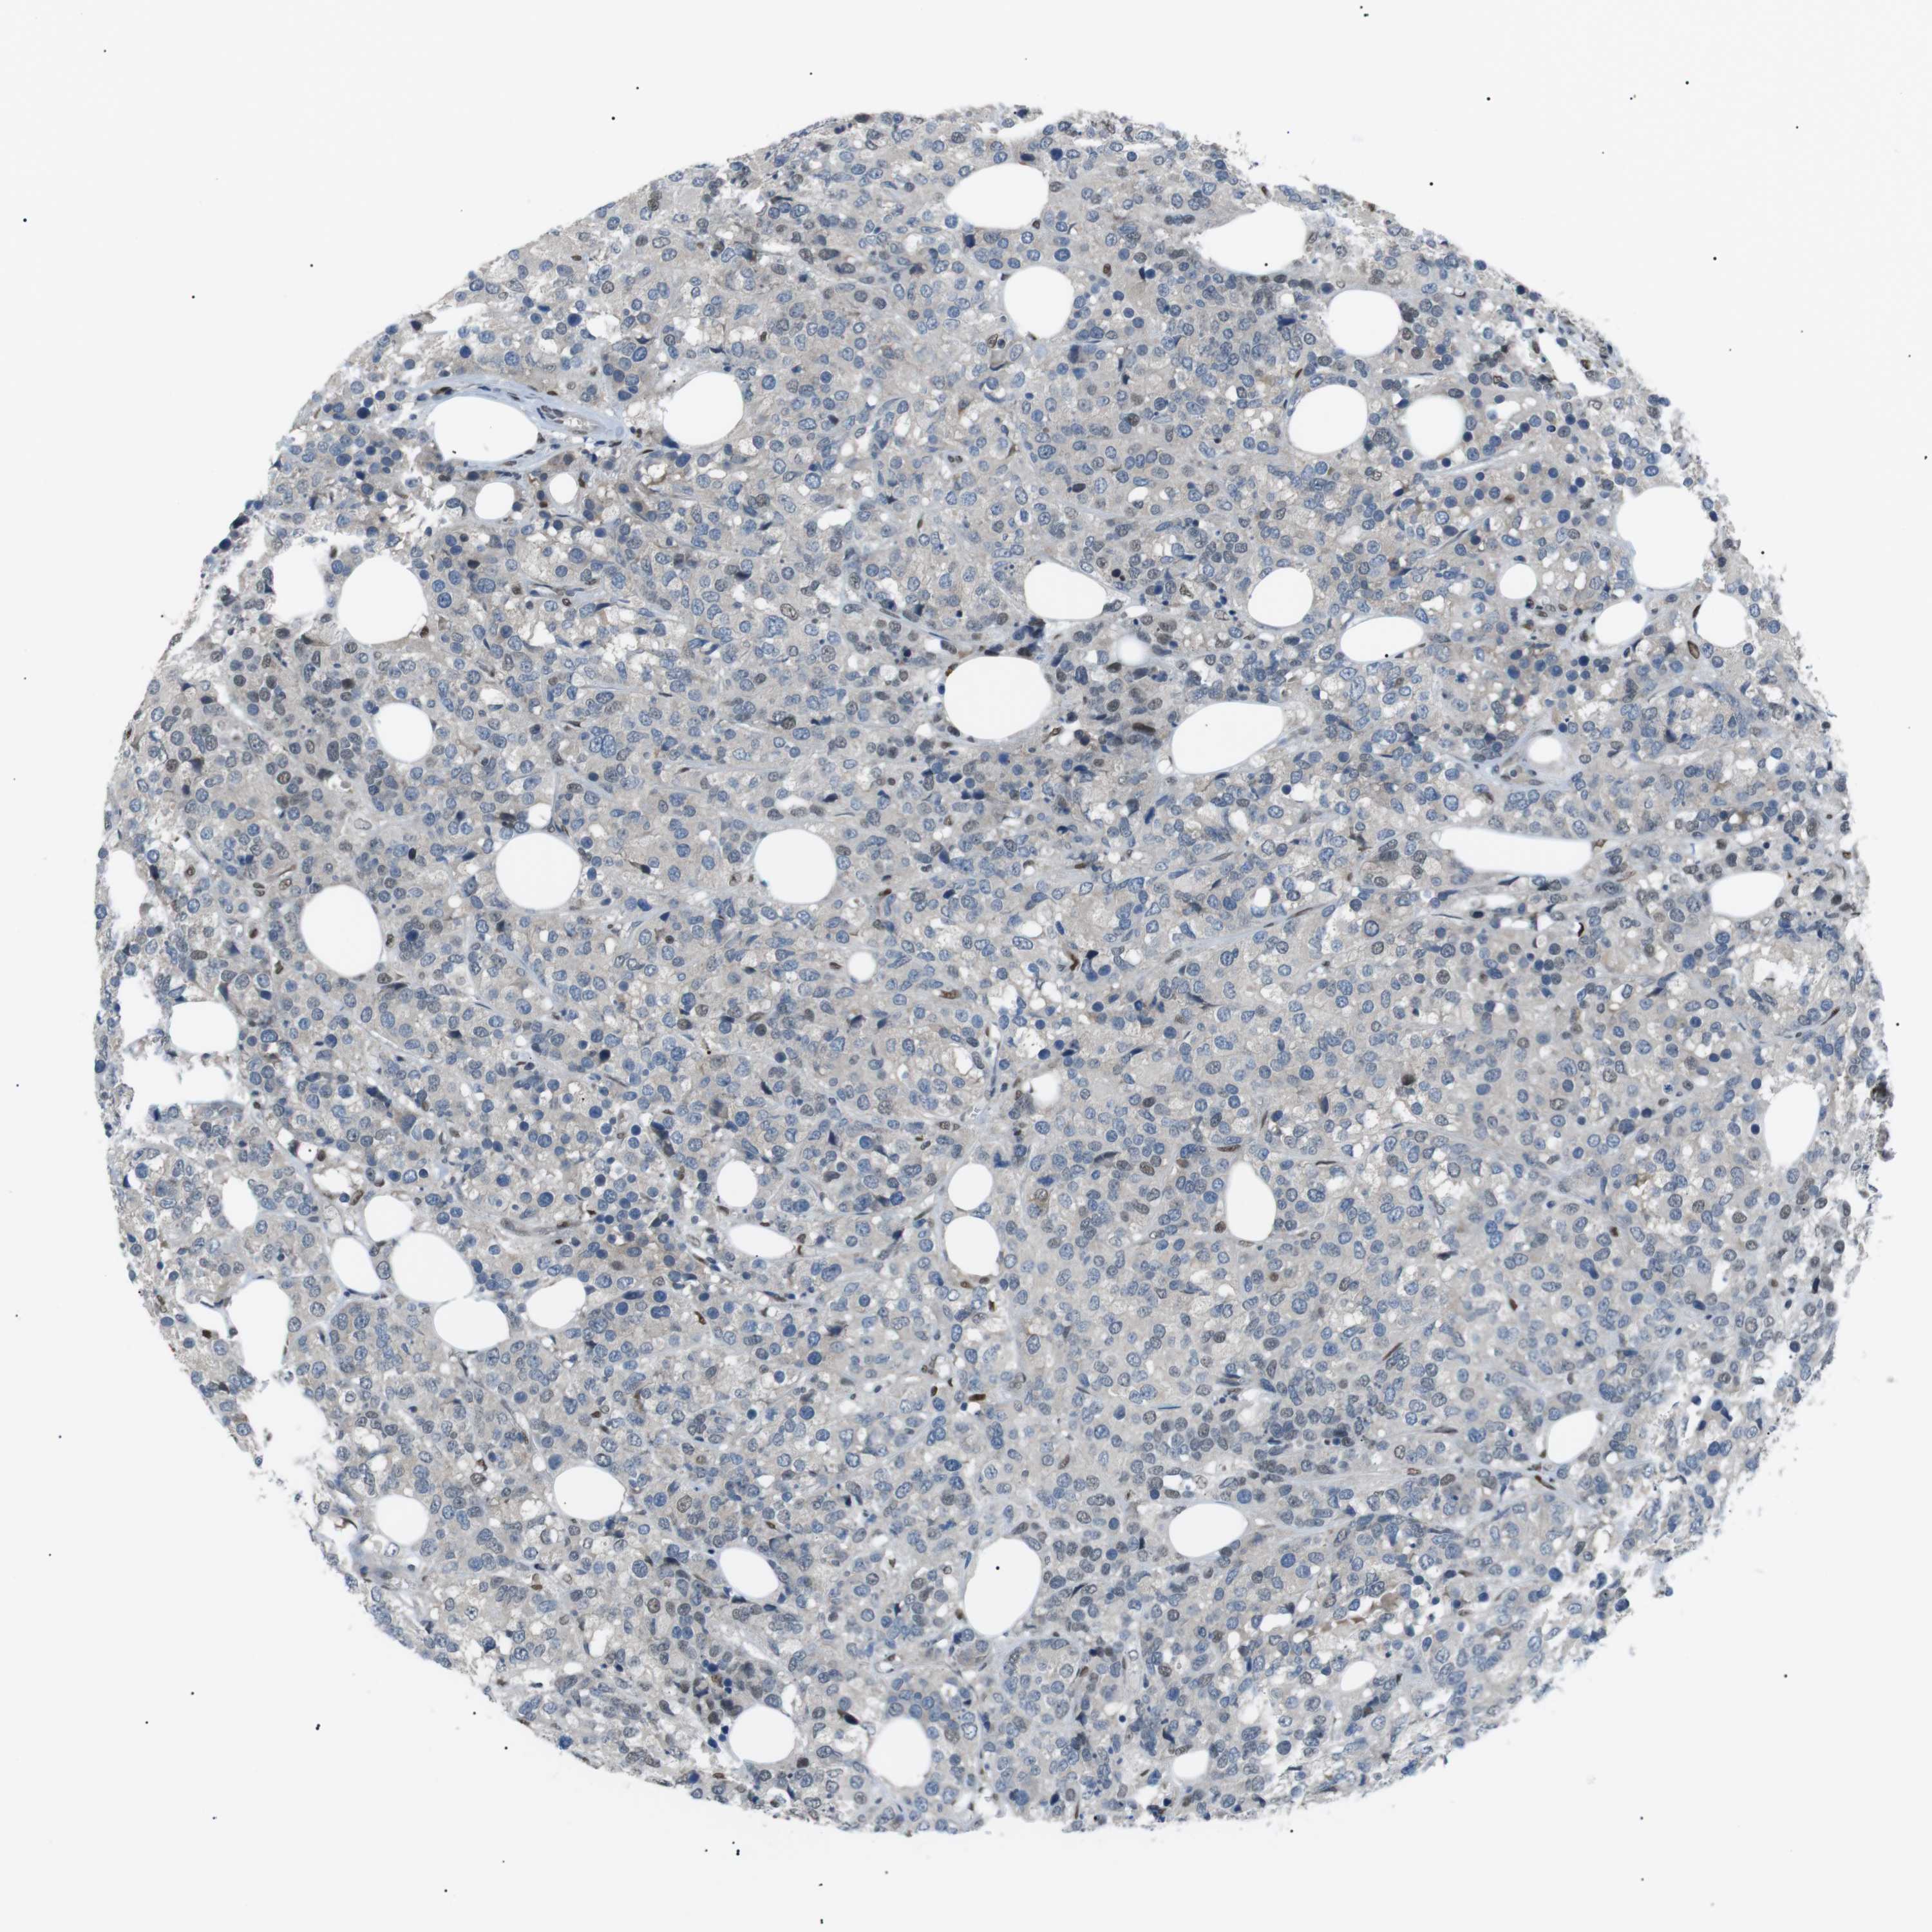

BRCA TCGA BRCA VALIDATION PROTEIN EXPRESSION